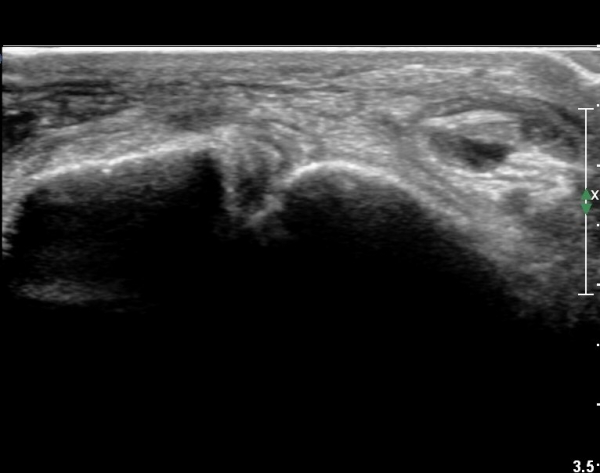

¹ß¸ñ ¾ÕÂÊ Á¾´Ü¸é°Ë»ç¿¡¼­ ¹ß¸ñ°üÀý³» °æ¹ÌÇÑ ¼ö¾×Àú·ù¸¦ º¸À̰í(»çÁø 1, 2)